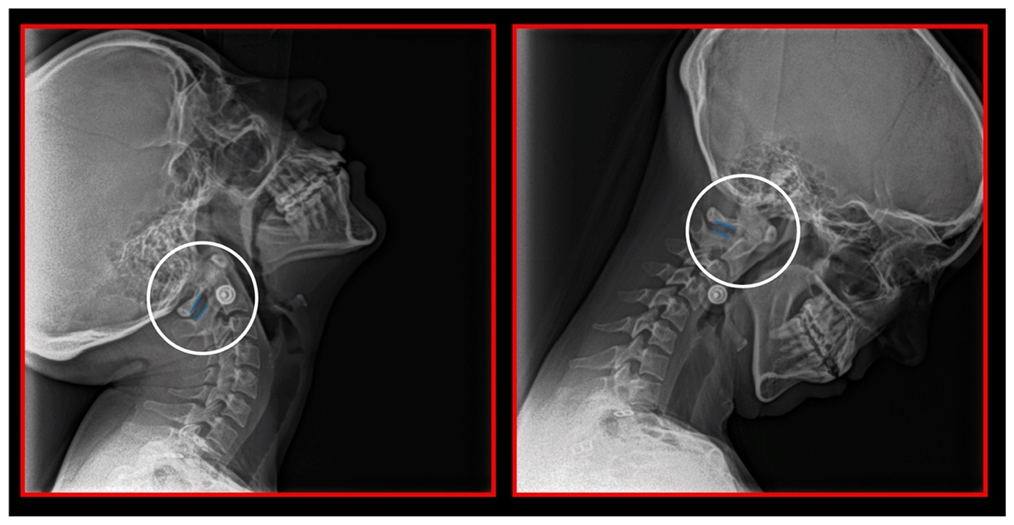

10.1. Neck X-ray

11.5. Axis and Atlas Derotation